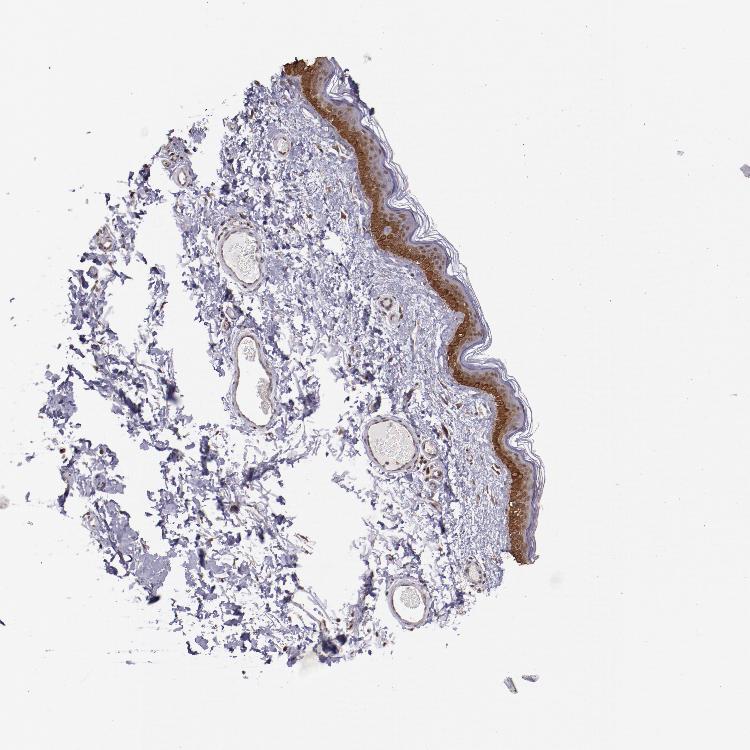

SKIN 2 - Antibody stainingi

Antibody staining in the annotated cell types in the current human tissue is reported as not detected, low, medium, or high, based on conventional immunohistochemistry profiling in selected tissues. This score is based on the combination of the staining intensity and fraction of stained cells.

Each image is clickable and will lead to virtual microscopy that enables deeper exploration of all samples and also displays staining intensity scores, fraction scores and subcellular localization as well as patient and tissue information for each sample.

Antibody HPA001755Antibody CAB005172

Epidermal cells HighMedium